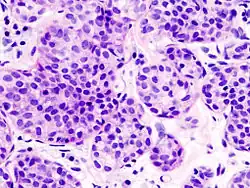

| Alveolar | 5% | Aggregates of classical-appearing cells | |

Histopathology of invasive lobular carcinoma (ILC), next to lobular carcinoma in situ (LCIS) -

Invasive lobular carcinoma demonstrating a predominantly lobular growth pattern -

Lobular breast cancer. Single file cells and cell nests. -

ILC may be subtle on low magnification (left). Higher magnification (right) shows invasive growth pattern and vesicular nuclei with prominent nucleoli.